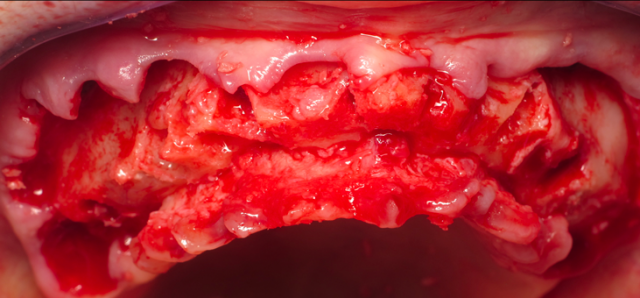

1. The majority of our space is achieved through an aggressive alveolar reduction. Prior to extracting teeth but after the muco-periosteal reflection is completed, I will anatomically indicate the vertical reduction on the alveolus.

Using calipers set at 15 mm, I will measure from the incisal edge or buccal cusp tips and mark the alveolus. After the teeth are removed, then the bone reduction is completed down to the indicated marks, and I then have created the required space.

If the existing teeth are in the wrong position in the face, this needs to be taken into account for the calculation. I address these cases in an aggressive nature and will consider bone “as the enemy.” It’s an unnatural way for us in implant dentistry to “feel” about bone. But the consequences of leaving too much bone height is devastating to the patient’s final outcome with a fixed hybrid prosthesis.